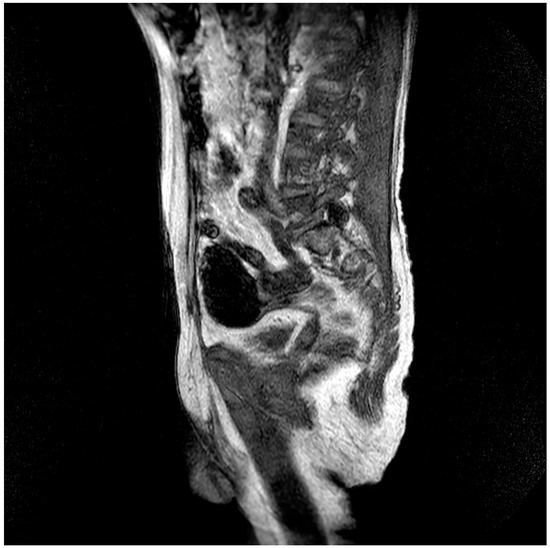

| Pt 7, M, 71, 2025 | HHD, cognitive involutional syndrome | High fever, headache, confusion, worsening motor difficulty with lower limb weakness | +/+ | Neg | Neg | Neg | ICH of the occipital horns of the lateral ventricles (Figure 2) | Diffuse meningoencephalitis, with involvement of the cauda extremity roots. ICH of the occipitopolar and bihemispheric mid-posterior cingulate sulci, the left temporoparietal carrefour, and the fourth ventricle, occipital horns, and pericerebellar cistern. Posterior dorso-lumbo-sacral, anterior dorso-lumbar (up to L1), and sacral epidural hematoma (Figure 3 and Figure 4) | DEX, Igs | Gradual clinical improvement, however lower limb weakness persisted | Transferred to a rehabilitation facility 34 days after hospital admission. | |

Figure 2.

Evidence of an extensive epidural spinal cord hematoma on spinal MRI (Table 1, patient 7).